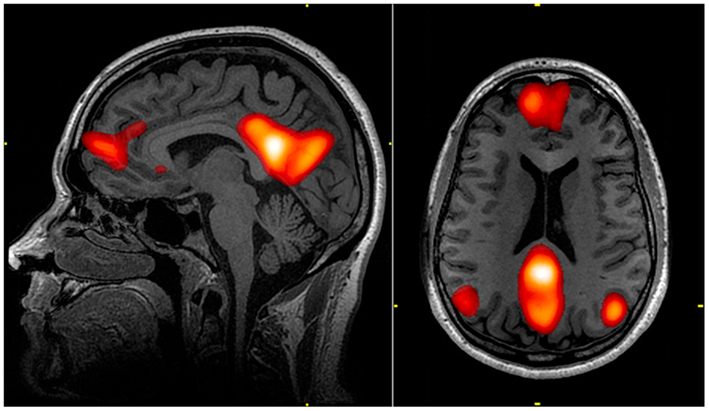

🔹 1. DMN(디폴트 모드 네트워크) — 무의식의 작업실

DMN은 우리가 멍하니 있거나

아무것도 하지 않는 것처럼 보일 때

오히려 가장 활발해지는 뇌 네트워크다.

이때 뇌에서는 다음과 같은 작업이 이루어진다.

- 과거 경험 정리

- 감정 재구성

- 자아 이미지 유지

- 미래 시나리오 연결

- 삶의 의미 해석

즉, DMN은

‘지금 당장 행동하지 않을 때’ 삶의 방향을 조율하는 공간에 가깝다.

그래서 생각이 많아지는 시간은

게으름이 아니라

무의식이 바쁘게 일하고 있는 시간일 수 있다.